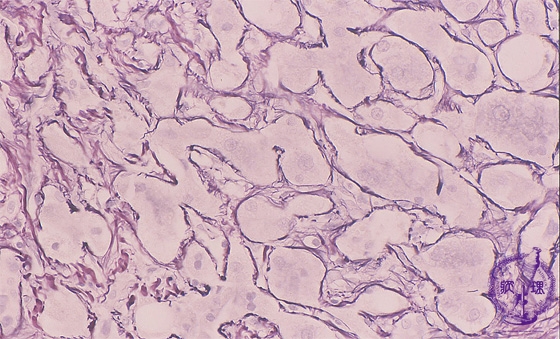

• š(2)Alcoholic hepatitis, cirrhosis

Microscopic image (silver stain, high power): Hepatocytes show distinct centrilobular perisinusoidal fibrosis, consistent with alcoholic steatohepatitis. The hepatocellular architecture is distorted.